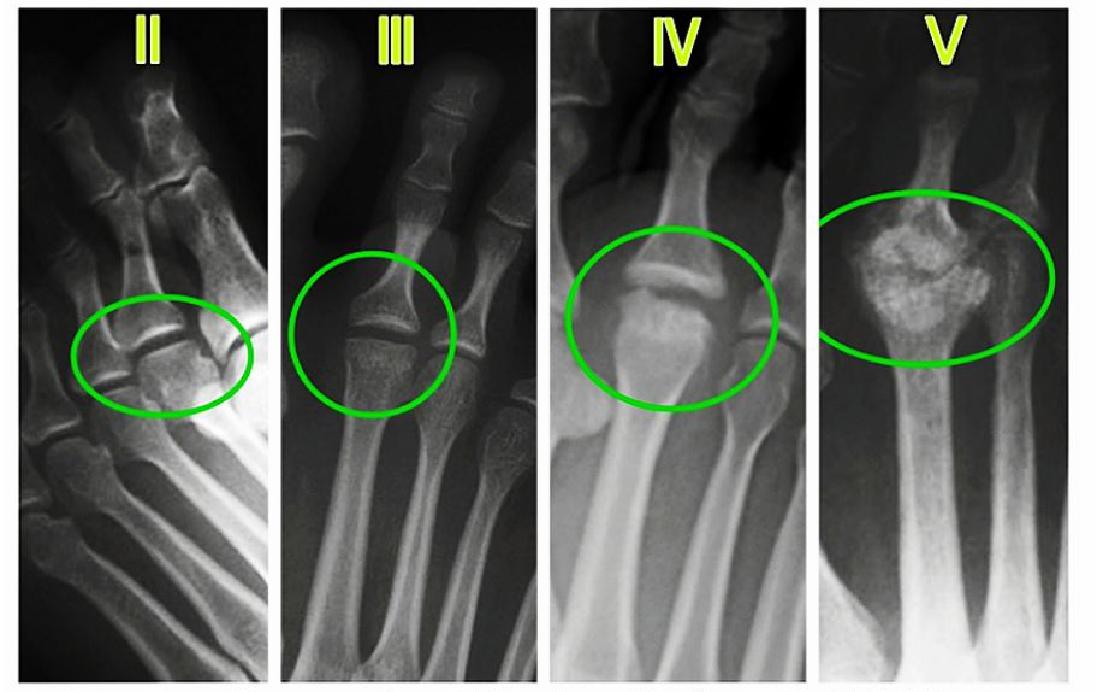

★Smillie于1967年根据病理变化将Freiberg病分为5期,这是目前临床最常用的临床分期方法,对指导治疗和判断愈合具有十分重受作用。

影像学表现?你看出区别了吗?(结合上面个分级表,你也可以当医生了哦)

Smillie于1967 年根据病理变化将Freiberg 病分为5期,这是本病最早、目前使用最广泛的分期。

Freiberg病早期(Ⅰ期)不易被发现,患者常无症状,或仅有不适感。X线检查无法发现异常,MRI可发现早期变化。Ⅰ期患者在临床上难发现,临床上常发现Ⅱ~Ⅴ期患者。

Ⅱ、Ⅲ期患者年龄集中在16~25岁,这类患者病情进展较为缓慢,病程持续10余年才进展到Ⅳ期甚至Ⅴ期。对于此期患者,常采取保留关节的手术方式,通过重新建立关节匹配性,能够重塑跖骨头外形。